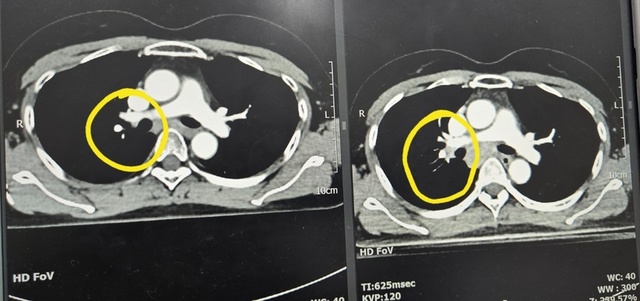

불청객

작아진 불청객

32횟차

33회차를 먼제 하나 했는데드뎌내일로 끝오늘은 교수님외래결과가 좋기를 기도

방사선치료12회차

방사선치료 7일차